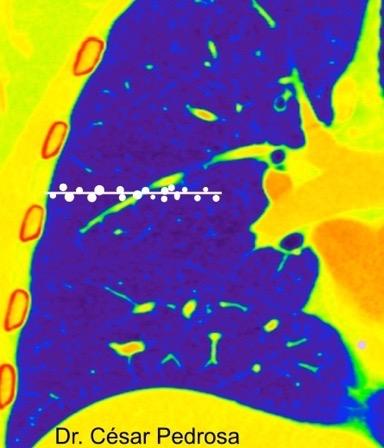

BORDE RECTO. “SIGNO DEL

(Straight edge sign)

La ausencia uni o bilateral de un límite bien definido de la panalización en cortes coronales ha sido asociada a la neumonitis intersticial usual.(NIU)

Bilateral: (Valor predictivo positivo 96,7).

Fibrosis pulmonar NIU por biopsia. Signo del borde recto en el lado derecho.

Zhan X et al. Differentiating Usual Interstitial Pneumonia From Nonspecific Interstitial Pneumonia Using High-resolution

Computed TomographyThe “Straight-edge Sign”. Journal of Thoracic Imaging: 2018